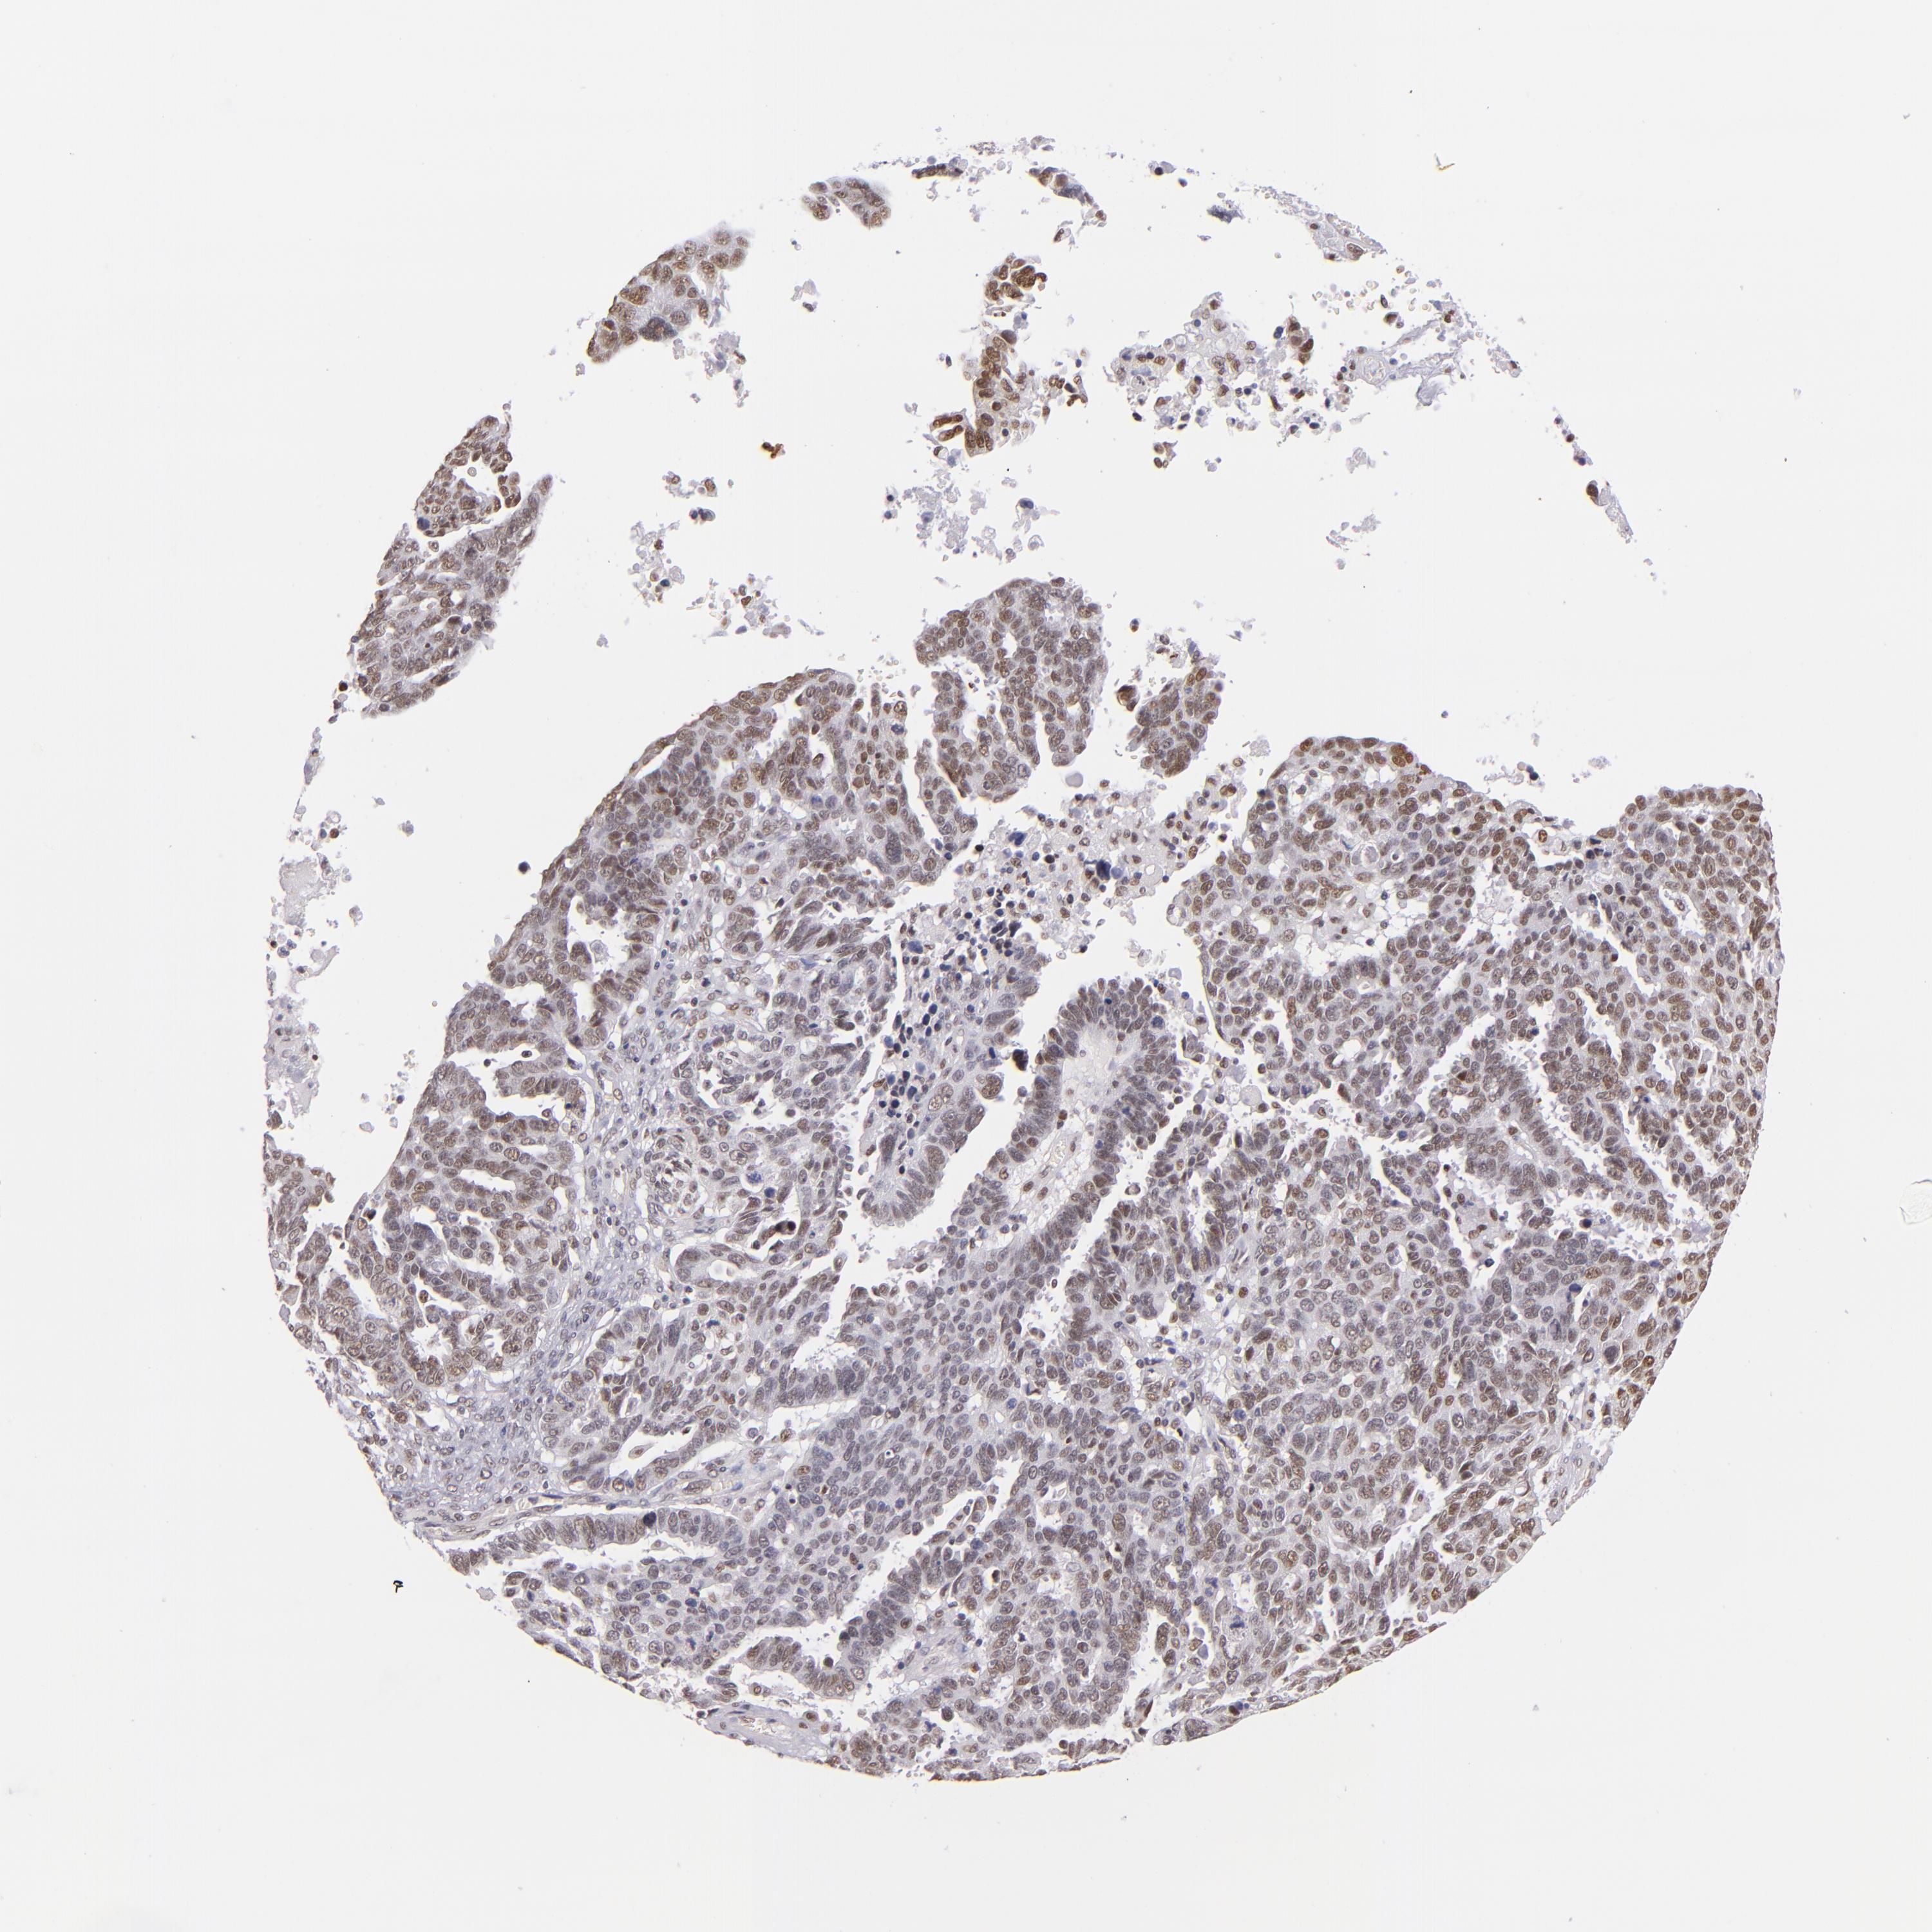

OVARIAN CANCER - Protein expressioni

A mouse-over function shows sample information and annotation data. Click on an image to view it in a full screen mode. Samples can be filtered based on level of antibody staining by selecting one or several of the following categories: high, medium, low and not detected. The assay and annotation is described here.

Note that samples used for immunohistochemistry by the Human Protein Atlas do not correspond to samples in the TCGA dataset.

Antibody stainingi

Antibody staining in the annotated cell types in the current human tissue is reported as not detected, low, medium, or high, based on conventional immunohistochemistry profiling in selected tissues. This score is based on the combination of the staining intensity and fraction of stained cells.

Each image is clickable and will lead to virtual microscopy that enables deeper exploration of all samples and also displays staining intensity scores, fraction scores and subcellular localization as well as patient and tissue information for each sample.

Antibody HPA001928

Staining

High

Medium

Low

Not detected

Intensity

Strong

Moderate

Weak

Negative

Quantity

>75%

75%-25%

<25%

None

Location

Nuclear

Cytoplasmic/membranous

Cytoplasmic/membranous,nuclear

Carcinoma, endometroid

Cystadenocarcinoma, serous, NOS

Cystadenocarcinoma, mucinous, NOS